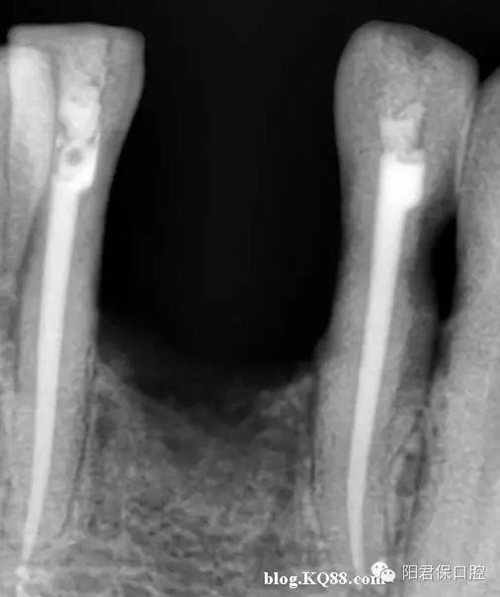

患者:姜XX 性別;女 年齡:65 根據(jù)齲壞程度、患者的癥狀、修復(fù)需要,且對收費及牙髓處理均征得同意后第一次行右下4、5,左下4、5、6;第二次行左下2,右下2 ,右上7一次性根管治療術(shù)。

術(shù)后見右下4,左下4均有側(cè)支充填,且位置對稱,左下6近中根中部有側(cè)支;左下5、左下6遠中根管均多個開口。

熱牙膠垂直加壓后有封閉劑和牙膠超填,但無術(shù)后反應(yīng)。